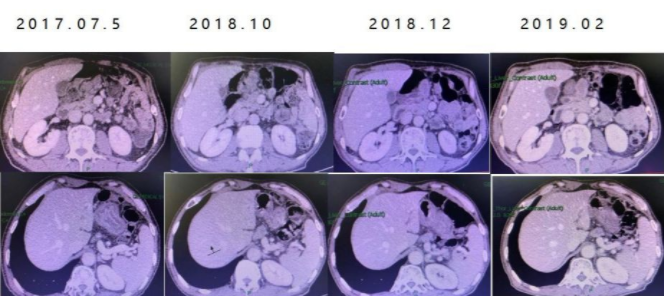

患者神经毒性基本恢复,于2016.09启动“FOLFOX+曲妥珠单抗”联合治疗,共12周期,整体疗效SD。

2017.02行胃区局部放疗。

2017.05给予“替吉奥+曲妥珠单抗”维持治疗。

阶段-4治疗及评估

2018.10再次影像学评估为PD,给予IRI单药化疗10周期,疗效评价SD。

2019.03~2019.06给予卡培他滨维持治疗后PD,暂未治疗。

小结:患者腔镜探查为不可切除IV期胃癌,经多程化疗联合抗HER2靶向治疗,耐受性良好,目前(2019.06)总生存达61个月。一线方案为“XELOX+曲妥珠单抗”8周期,“卡培他滨+曲妥珠单抗”维持治疗5月余,神经毒性2级;二线方案为“DS+曲妥珠单抗”8周期,并给予“替吉奥+曲妥珠单抗”维持治疗6月余;三线方案为“FOLFOX+曲妥珠单抗”12周期后,给予放疗治疗,“替吉奥+曲妥珠单抗”维持治疗16月发生进展;四线方案为IRI单药化疗10周期,卡培他滨维持治疗4月发生进展。